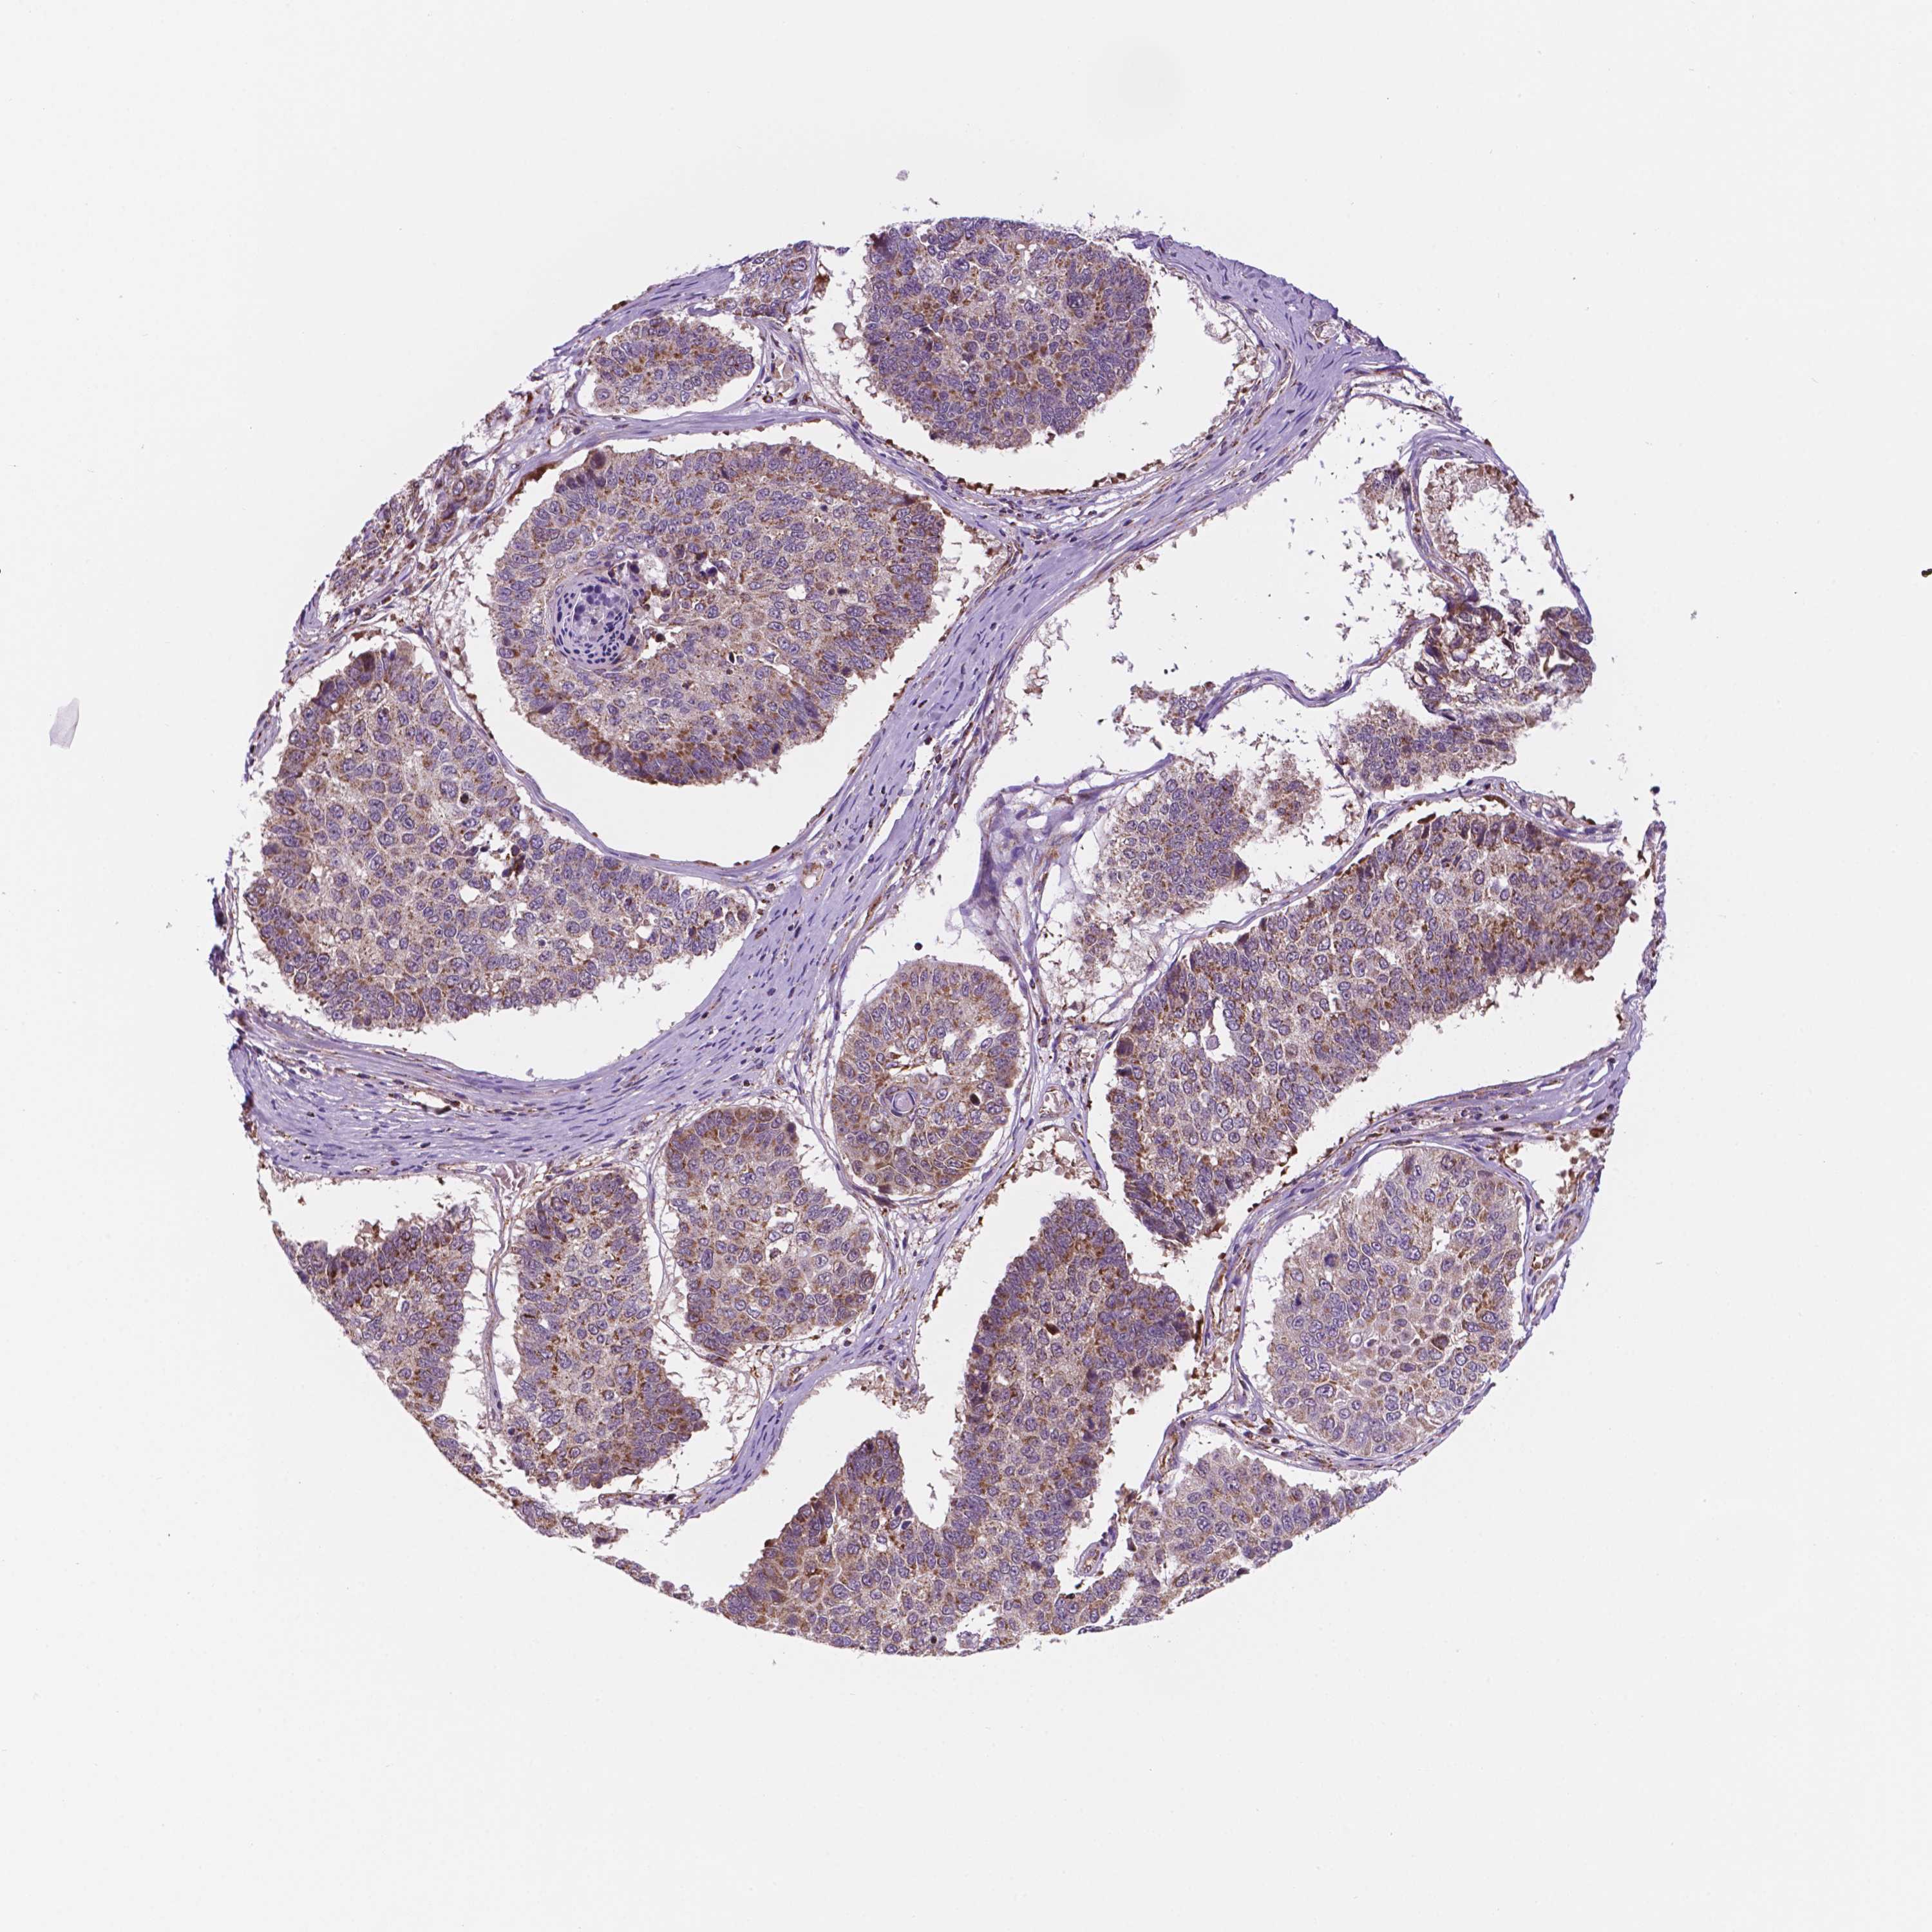

LUNG SQUAMOUS CELL CARCINOMA (TCGA) - Interactive survival scatter ploti

The Survival Scatter plot shows the clinical status (i.e. dead or alive) for all individuals in the patient cohort, based on the same data that underlies the corresponding Kaplan-Meier plots. Patients that are alive at last time for follow-up are shown in blue and patients who have died during the study are shown in red.

The x-axis shows the expression levels (FPKM) of the investigated gene in the tumor tissue at the time of diagnosis. The y-axis shows the follow-up time after diagnosis (years). Both axes are complimented with kernel density curves demonstrating the data density over the axes. The top density plot shows the expression levels (FPKM) distribution among dead (red) and alive patients (blue). The right density plot shows the data density of the survived years of dead patients with high and low expression levels respectively, stratified using the cutoff indicated by the vertical dashed line through the Survival Scatter plot. This cutoff is automatically defined based on the FPKM cutoff that minimizes the p-score. The cutoff can be changed by dragging the vertical line or by entering a cutoff value in the square labeled "Current cut-off".

Under the Survival Scatter plot the p-score landscape (black curve; left axis) is shown together with dead median separation (red curve; right axis). Dead median separation is the difference in median mRNA expression between patients who have died with high and low expression, respectively. It is calculated as follows: median FPKM expression of dead patients with high expression - median FPKM expression of dead patients with low expression. This is intended to aid the user in visually exploring custom cutoffs and the associated p-scores and dead median separation.

Individual patient data is displayed and can be filtered by clicking on one or more of the category buttons on the top of the page. Categories describing expression level and patient information include: high, low, alive, dead, female, male and tumor stages. The scale of the x-axis can be toggled between linear and log-scale by clicking on the "x log" button. Mouse-over function shows TCGA ID, patient information and mRNA expression (FPKM) for each patient.

& Survival analysisi

Kaplan-Meier plots summarize results from analysis of correlation between mRNA expression level and patient survival. Patients were divided based on level of expression into one of the two groups "low" (under cut off) or "high" (over cut off). X-axis shows time for survival (years) and y-axis shows the probability of survival, where 1.0 corresponds to 100 percent.

GEMIN4 is not prognostic in Lung Squamous Cell Carcinoma (TCGA)

: 12.8

P scorei

N/A

Average pTPM 16.6

Number of samples 489